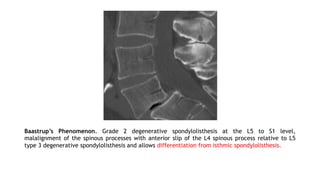

Baastrup’s Phenomenon. Grade 2 degenerative spondylolisthesis at the L5 to S1 level,

malalignment of the spinous processes with anterior slip of the L4 spinous process relative to L5

type 3 degenerative spondylolisthesis and allows differentiation from isthmic spondylolisthesis.

• Baastrup’s phenomenon,also known as kissing spine • Pain caused by irritation of the periosteum or adventitial bursae between abutting spinous processes. • Close approximation and contact of the adjacent spinous processes with enlargement, flattening and reactive sclerosis of the opposing interspinous surfaces. • Interspinous bursitis may communicate with the facet joints and can be treated with injection of steroids. • Extension of the synovial cavity to the intraspinal space can result in cyst formation⇒can enter the epidural space via midline cleft of LF ⇒ extradural compression. Spinous Process Abnormalities and Associated Ligamentous Changes

Baastrup’s Phenomenon. Grade2 degenerative spondylolisthesis at the L5 to S1 level, malalignment of the spinous processes with anterior slip of the L4 spinous process relative to L5 type 3 degenerative spondylolisthesis and allows differentiation from isthmic spondylolisthesis.